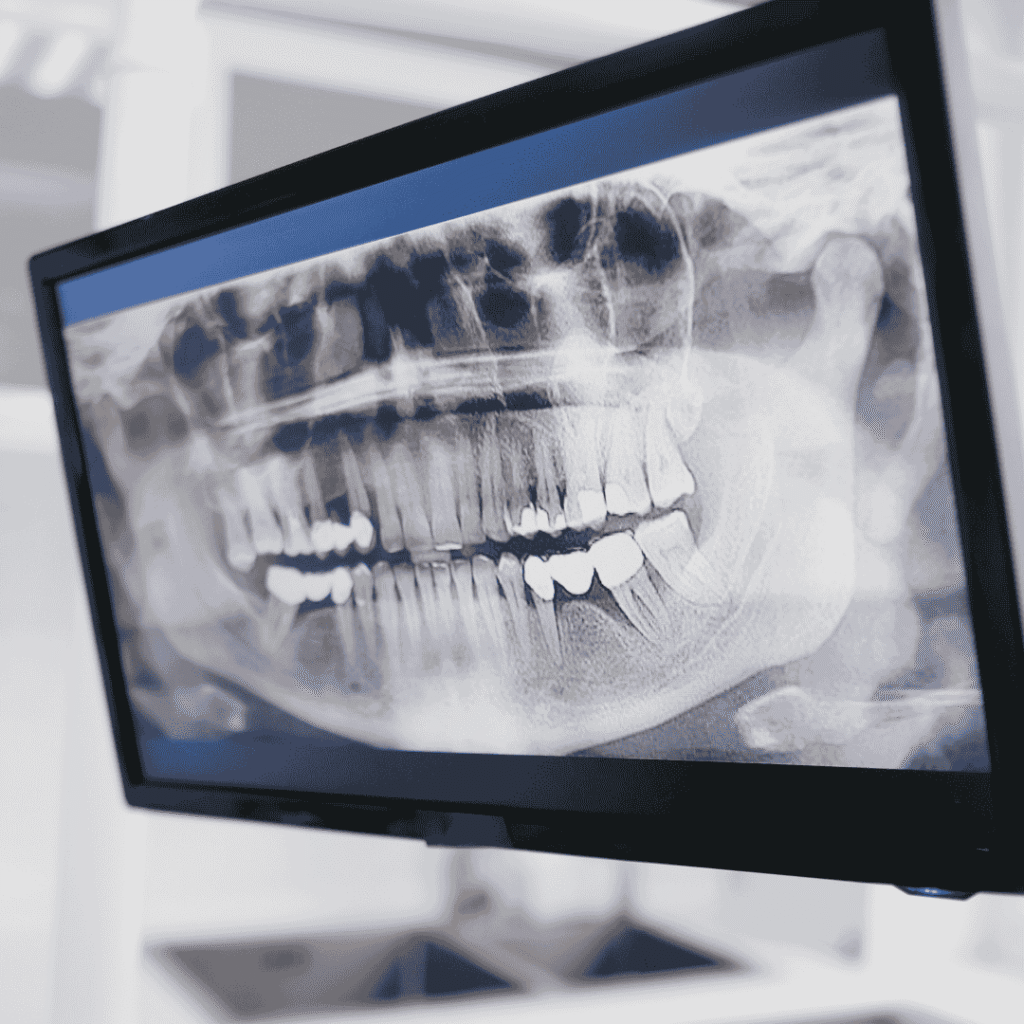

- Advanced Infrastructure: Clinics like Esthetica Dental utilize 3D CBCT imaging, digital impressions, and AI-driven treatment planning.

- Virtual Consultation: We review your OPG or CBCT scans remotely and provide a detailed quote before you fly.

- Arrival & Assessment: Once in Mohali, we perform a physical examination and 3D digital scan.